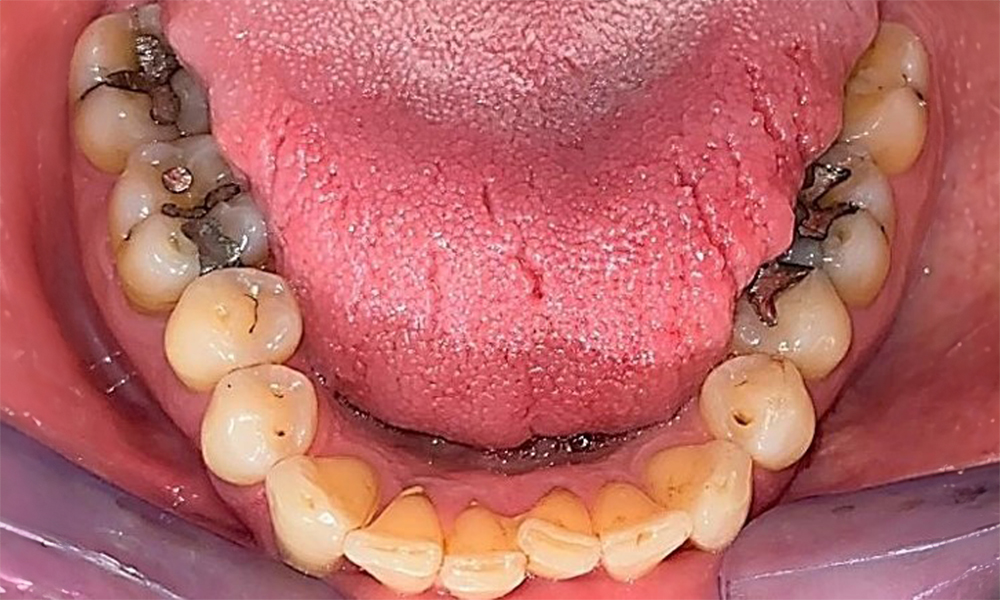

Dentaler Befund

Der Patient hat ein vollbezahntes Gebiss mit 28 Zähnen, an welchen sich im Molaren- und Prämolarenbereich Amalgamfüllungen und Compositefüllungen befinden. An Zahn 14 zeigt sich ein sichtbarer klinischer Randspalt. Zahn 27 hat ein suffizientes Goldinlay. Zudem zeigen sich generalisierte Attritionen und Abrasionen. (Abb. 2, Abb. 3, Abb. 4, Abb. 5, Abb. 6)

Der Patient hat eine Parodontitis Stadium II, Grad B (5). Die klinischen Sondierungstiefen liegen mit 1-3mm im physiologischen Bereich. Lokalisierte Sondierungstiefen finden sich an 17 und 27 jeweils mesiopalatinal mit 5mm. Es liegen generalisierte Rezessionen von 1-3mm vor mit partiellem Verlust der Interdentalpapillen (Abb. 2, Abb. 3, Abb. 4)